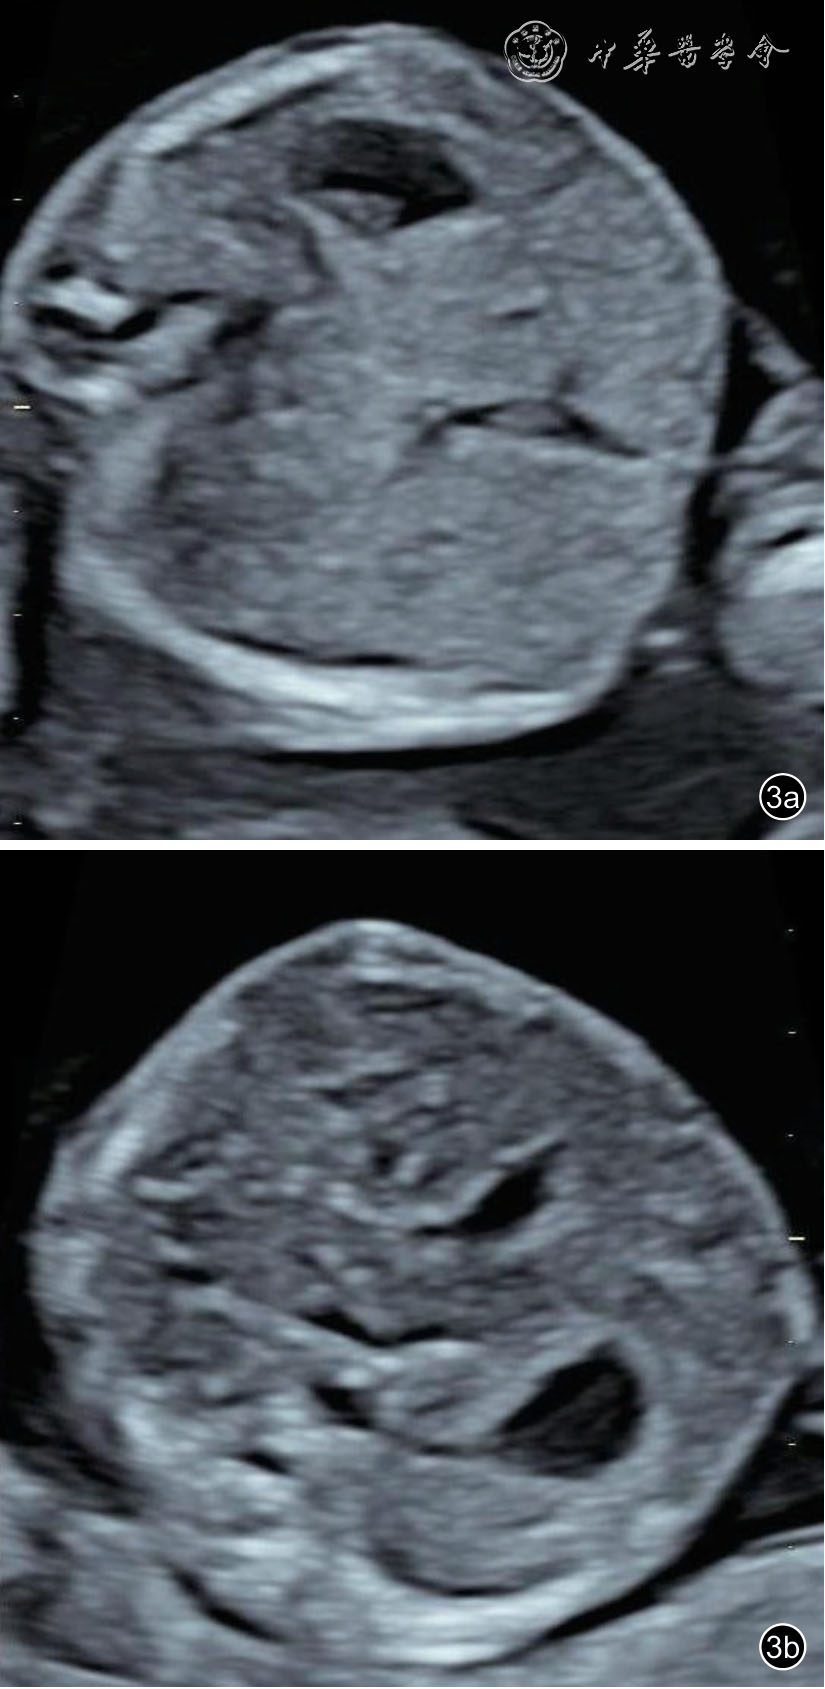

26 例TAPS 均在中晚孕期(孕17+1~34+6 周)超声检查中发现,其中Ⅰ期11 例,Ⅱ期3 例,Ⅲ期3 例,Ⅳ期9 例,Ⅴ期0 例。共有的超声特征为:(1)供血儿MCA-PSV 增高(>1.5 MoM),受血儿MCA-PSV 降低(<1.0 MoM)( 图1);(2)“黑白”胎盘:供血儿脐带入口附近胎盘回声增强、增厚,受血儿脐带入口附近胎盘回声减低、较供血儿侧薄(图2)。其他超声特征包括:(1)24例(92%)受血儿肝呈“星空征”(图3);(2)4例(15%)供血儿肠管回声增强(图4);(3)22例(85%)心脏异常,包括心胸比增大、房室瓣反流、房室瓣频谱呈单峰、心肌增厚等征象(图5a、5b);(4)18 例(69%)多普勒血流异常,包括脐动脉、脐静脉、静脉导管A 波异常等;(5)9 例(34%)胎儿水肿,包括皮肤水肿、胸腹腔积液、心包积液;(6)15 例(57%)羊水量不均衡;(7)19 例(73%)脐带异常,包括脐带水肿、脐带插入点异常(图6);(8)15 例(57%)合并双胎选择性宫内生长受限(selective intrauterine growth restriction,sIUGR)、TTTS(表1)。对供血儿及受血儿其他超声特征进行统计分析发现,受血儿肝“星空征”、脐带水肿,供血儿肠道回声增强、胎儿水肿、心胸比增大特征比较,差异有统计学意义(P<0.05,表2)。

图3 双胎贫血-红细胞增多序列征胎儿孕17+1 周产前超声图像可见供血儿(图a)肝回声稍增强,受血儿(图b)肝回声减低,管壁回声增强,呈“星空征”

本研究26 例病例,供血儿表现为MCA-PSV增高(>1.5 MoM),脐带插入点附近胎盘回声增强、增厚,肠道回声增强;受血儿表现为MCAPSV 降低(<1.0 MoM),脐带插入点附近胎盘回声减低,肝呈“星空征”,脐带直径增粗、水肿。TAPS 胎盘内血管吻合的特点导致供血儿侧胎盘有效绒毛数量及面积不足,绒毛间隙形成血栓、绒毛水肿,子宫胎盘间的血管床被破坏,胎盘物质交换受到影响,TAPS 双胎发生sIUGR、TTTS 的概率明显增加[14,15],本中心发生率约为57%。本文中TAPS 两胎儿均有心脏增大的表现,但供血儿发生率明显高于受血儿,因供血儿持续的缺血、缺氧,需要更高的心输出量才能为身体提供足够的血流量。本中心TAPS 受血儿肝“星空征”发生率达到92%,与国外文献[16]相比明显增高,这与胎儿检查孕周及检查医师的经验有一定关系。受血儿肝呈“星空征”表现的病理生理机制目前仍未明确,多数学者推断可能是由于受血儿红细胞过多,导致肝细胞水肿,肝回声弥漫性降低(空),与肝内血管壁(星)形成明显的差异[17]。而供血儿肠道回声增强可能原因是肠道血流灌注减少,导致肠道管壁缺血坏死[18]。本研究26 例TAPS 平均诊断孕周为25 周左右,与文献报道的TAPS 确诊孕周多数在26 周以后[19]有所差异,这可能与诊断医师的经验、是否加查大脑中动脉频谱及转诊的孕周等有关。